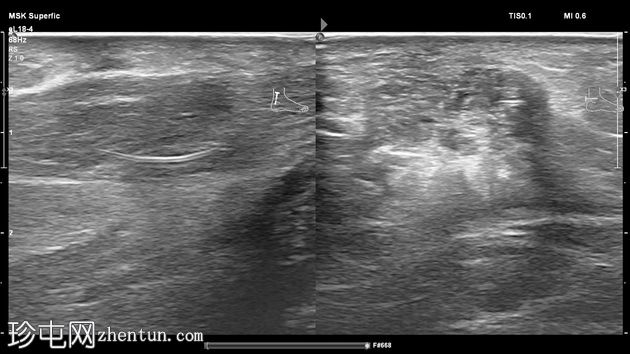

横位

左足跟皮下组织内可见一管状高回声物质,呈串珠状,与手术缝线相符,周围环绕着低回声积液。与缝线相连的是一根细细的、呈轨道状的高回声合成单丝,它穿过跟腱呈弧形走行,该缝线为不可吸收缝线。